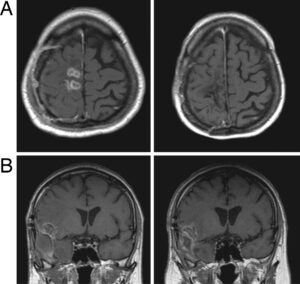

Tumor treating fields therapy device for glioblastoma: physics and clinical practice considerations Edwin Lok1, Kenneth D Swanson1 and Eric T Wong*1,2 ... Read Content